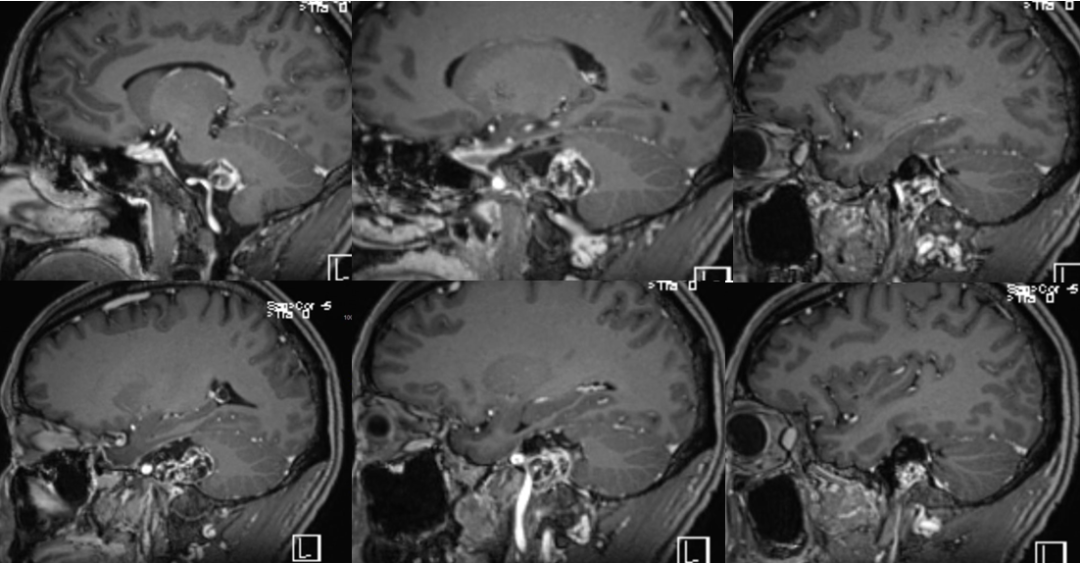

术前影像

![]()